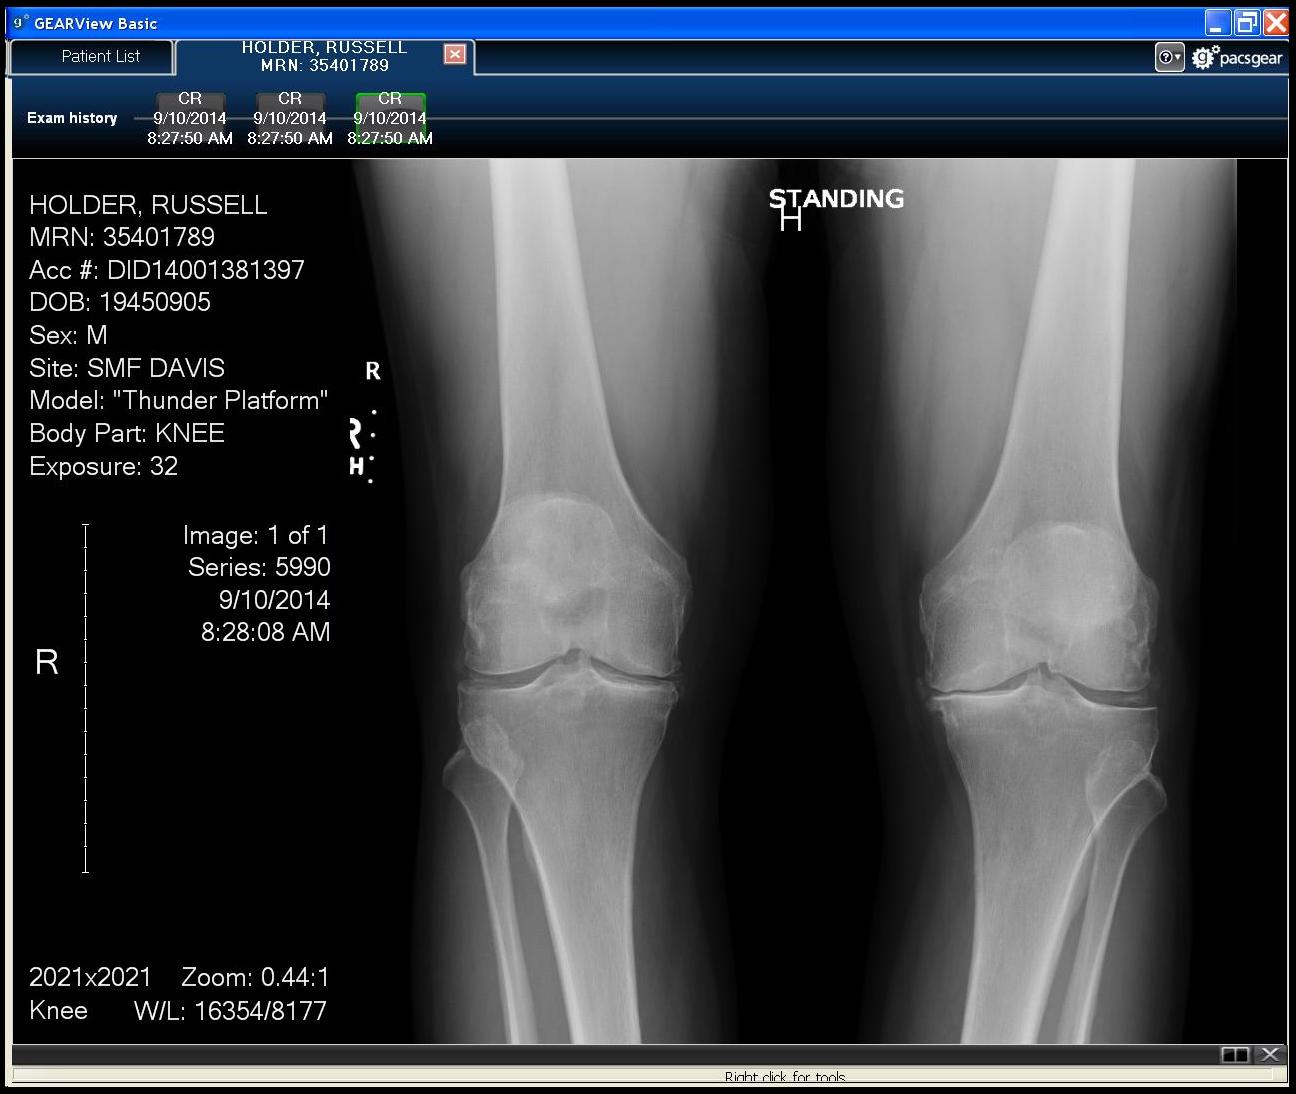

During 2014 I was experiencing a lot of pain in my knees, in particular, in my left knee. On September 10th 2014 weight bearing X-rays taken of my knees (see image in the link below) revealed no gap between femur and tibia on left knee (there s/b a gap), and, notice whitening of bones where they wee touching (because they had been beating on each other for a while). The doctor said I needed a total knee joint replacement on my left knee, and, my right knee was also bad and I would know how soon I wanted it replaced after getting the left knee replaced, I said not yet - I had found Aleve pain medication, he said call him when Aleve didn't work anymore. Aleve was helped with the pain in my left knee for a while before becoming unable to walk and on March 17, 2015 the total right knee joint was replaced at Sutter Davis Hospital.

Weight bearing X-ray, 10SEP14, 04MAY15, 23MAY19 (click on X-ray to enlarge):

X-ray by Sutter Davis Hospital

view full size X-ray: ./images/140910_knee_weightBearing_print.jpg"... X-ray by Sutter Davis Hospital